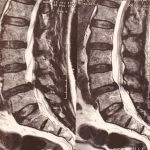

O Neurocirurgião especialista em coluna está apto a realizar o diagnóstico e tratamento de todos os problemas desse órgão, tanto o tratamento cirúrgico, quanto o clínico (tudo que não envolve cirurgias). Realiza o tratamento de doenças degenerativas (como hérnia de disco, estenose de canal lombar, espondilolistese), escoliose, tumores, fraturas, entre outros.